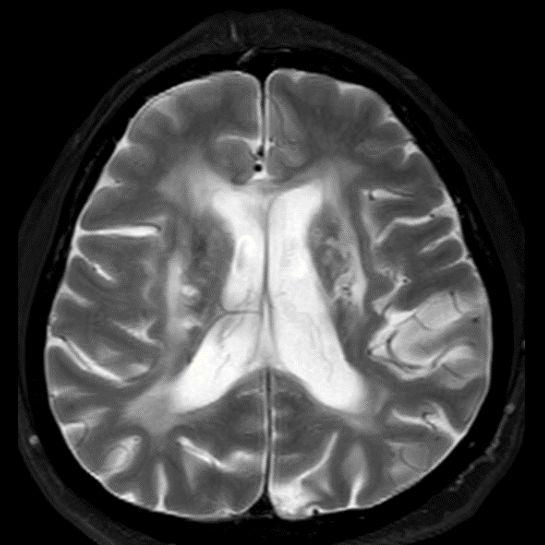

45 yaş, K

4 yıl önce akut sağ hemiparezi, konuşma bozukluğu ve dış merkezde serebellar iskemi tanısı ile ASA kullanımı öyküsü

Konuşma bozukluğu, yersiz gülme ve ağlama atakları, denge kaybı ve uyuşmaları devam ediyor

CADASIL

CADASIL SENDROMU